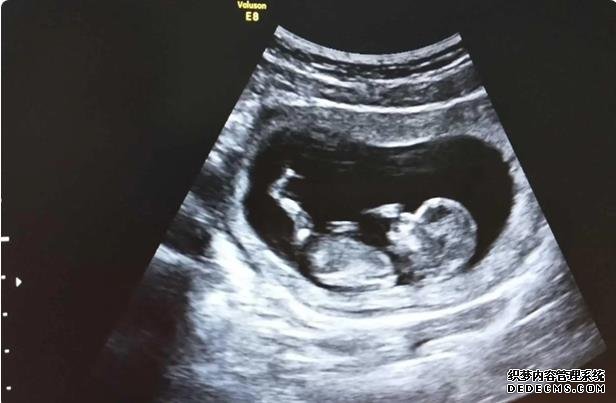

11.9号移植第二次,今天二次复查,千言万语总有说不出来的话,无从表达。不能说是血泪史,也是很坎坷,备孕,试管,都不容易。

第二次也很美(我现在的二婚),心里最柔软的地方还是自己的母亲,拿到成功的报告,抱着电话给老妈呜呜的哭,哭的不是自己受了多大委屈,而是一步步走过来,太不容易了。